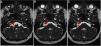

ResultsA total of 102 patients (63 women and 39 men) had vestibulocochlear involvement. The most common clinical indication was dizziness (41.18%). A unilateral vascular loop was found in 43 patients (right: 21.57%, left: 20.59%) and bilateral loops were found in 59 (57.84%) patients. The most common type of vascular loop was type II (right: 69.14%; left: 58.75%). The most common origin of vascular loops was the anterior inferior cerebellar artery (right: 66.67%, left: 65.00%). No associations were observed between vascular loops and sensorineural hearing, nystagmus, or vertigo. There was an association with tinnitus.

Resultados102 pacientes (63 mujeres y 39 hombres) presentaban afectación vestibulococlear. La indicación clínica más frecuente fue mareos (41,18%). Se halló asa vascular unilateral en 43 pacientes (derecho: 21,57%, izquierdo: 20,59%) y bilateral en 59 pacientes (57,84%). El tipo de asa vascular más frecuente fue el tipo II (derecho: 69,14%; izquierdo: 58,75%). El origen más frecuente fue la arteria cerebelosa anteroinferior (ACAI) (derecha: 66,67%, izquierda: 65,00%). No se observó ninguna asociación entre asas vasculares y pérdida de audición neurosensitiva, nistagmo o vértigo. Se halló una asociación con acúfenos.